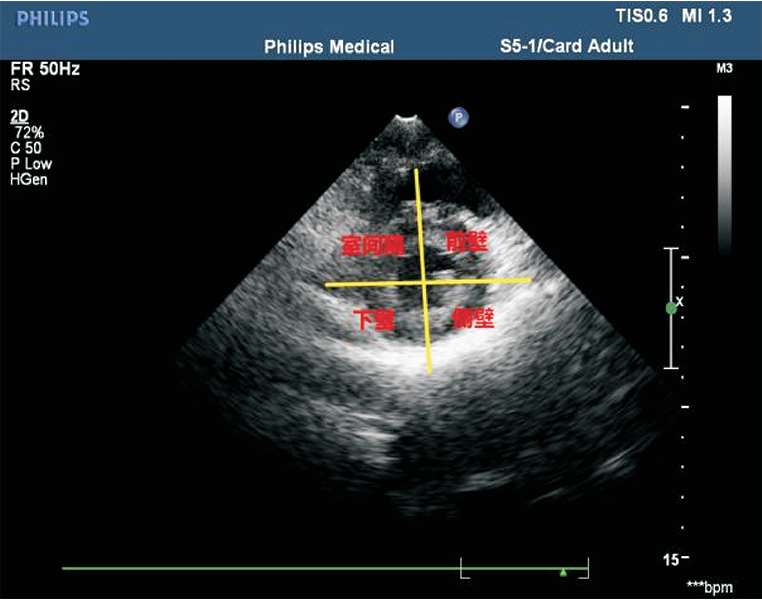

(7)常用的室壁分段方法为16段法。左心室长轴切面将左心室分为3等分:基底段、中间段及心尖段。基底段、中间段短轴切面分为6 等分:左心室前壁、左心室侧壁、左心室后壁、左心室下壁、后间隔及前间隔(见图1-38)。心尖段短轴切面分为4等分:左心室前壁、左心室侧壁、左心室下壁及室间隔(见图1-39)。

图1-38 基底段、中间段短轴切面分6等分

图1-39 心尖段短轴切面分4等分